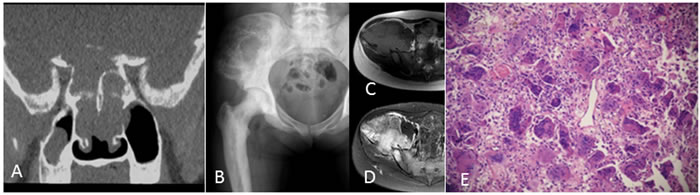

Figure 5: A 21-year-old woman with Paget‘s disease. A. Coronal reconstruction CT of the basicranial bone shows osteolytic destruction with soft tissue mass. B. Anteroposterior radiograph of the pelvis shows a large multilocular hypodense lesion at the iliac bone. C., D. MRI shows T1 intermediate intensity and T2 heterogeneous hyperintensity with a low stipe signal. E: Histologic appearance of a giant cell tumor of the bone at the iliac bone.

On radiographs (n = 14), 16 lesions manifested as geographic lucent lesions, and 1 lesion showed soft tissue density with stripe-like calcification (Figure 2B). Among these lesions, 9 lesions showed ring-like sclerosis (Figure 3B), 3 lesions showed patchy sclerosis (Figure 4E), and 4 lesions showed narrow transition without sclerosis (Figure 4B). Based on Campanacci et al’s grading system[23], 5 lesions were classified as grade III, 10 lesions as grade II, and 1 lesion as grade I. One lesion located in the calcaneus was treated with denosumab after one year, and a radiograph demonstrated shrinkage of the osteolytic zone and the formation of sclerosis in the center of the lesion and adjoining bone cortex (Figure 1D-1E). Four lesions showed increased sclerosis in the center and outer margin after six months.

On CT scanning (n = 13), 13 lesions showed marrow replacement by tissue with homogeneous attenuation, with homogeneity in 1 lesion. Nine lesions more clearly demonstrated sclerotic margins or patchy sclerosis (Figure 1A-1B). Three lesions showed a narrow transition without sclerosis. Eight lesions showed cortical discontinuity, and 5 lesions showed soft tissue mass throughout the bone cortex. Two lesions were treated with denosumab after four months; CT showed ring-like sclerosis around the outer margin (Figure 4H-4I) and increased sclerosis in the center of the lesion (Figure 4J-4K).

On MRI (n = 8), 2 lesions showed marrow replacement by homogeneous tissue, and 6 lesions showed marrow replacement by heterogeneous tissue on T1-weighted images. Two lesions had intermediate signal intensity (similar to that of the muscle), and 3 lesions showed predominately intermediate signal intensity with patchy or stripe-like low signal intensify (Figure 5C); 2 lesions showed mildly higher intensity than muscle, and 1 lesion showed low signal intensity on T1-weighted MR images (Figure 4F). On T2-weighted MR images, the signal intensity was heterogeneous in 6 lesions and homogeneous in 2 lesions. Five lesions showed predominately high signal intensity (similar to that of fat) with patchy or stripe-like low signal intensity (Figure 5D), and 1 lesion showed higher signal intensity than that of fat; 2 lesions showed homogeneous high signal intensity (Figure 4C). One lesion subjected to contrast enhancement showed obvious enhancement. In addition, cortical destruction with an associated soft tissue mass and extensive edema was seen 3 lesions.